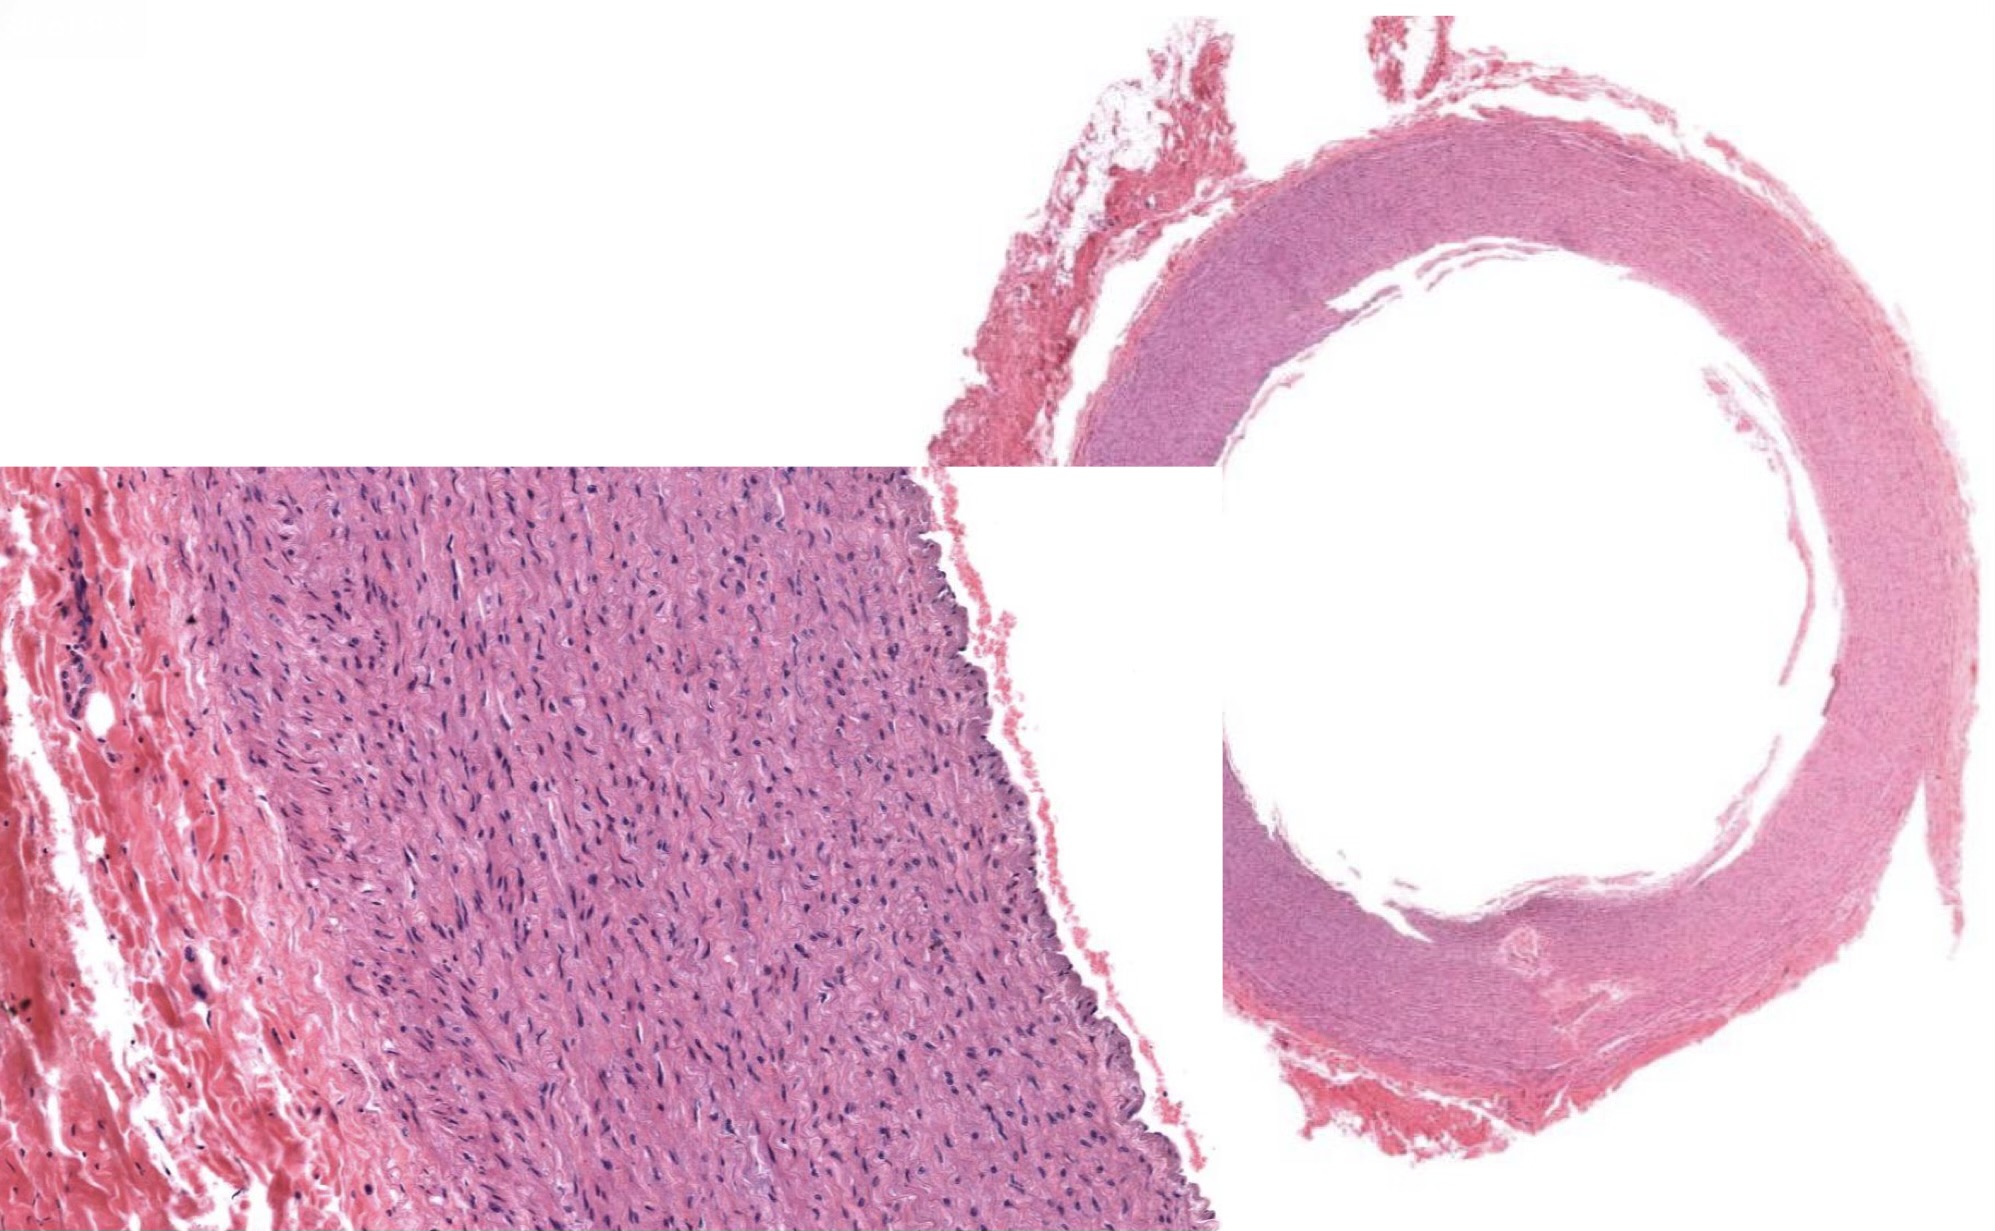

Idenitfy the Vessel and what are the Properties?

Large/Elastic Artery

close to heart

Ti made of endot + elastin + collagen

Tm made of elastic F + collagen; Smooth M!

Te made of DICT w/ vasa vasorum